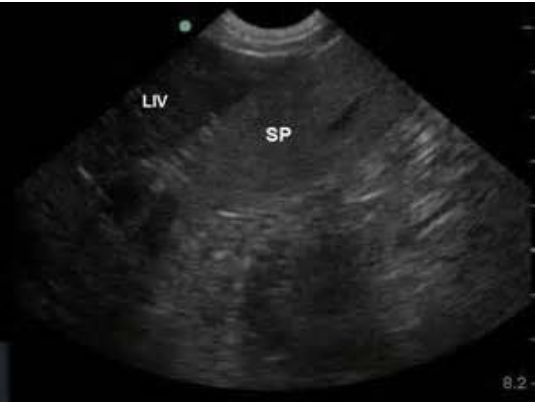

Spleen

elliptical, flat, with smooth contours

more echogenic than liver

may see splenic sinusoids